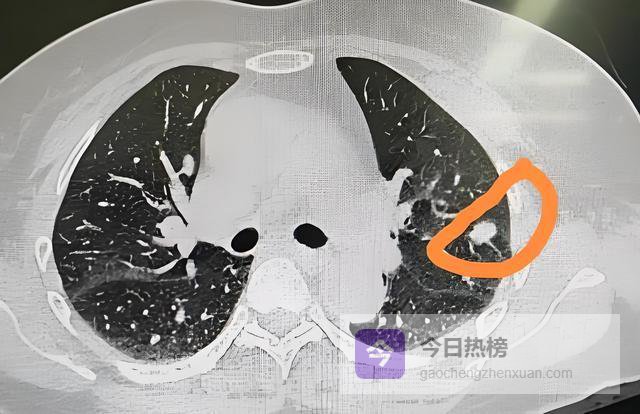

“磨玻璃影”(Ground-GlassOpacity,GGO)之所以令人关注,是因为它往往代表肺泡壁增厚、细胞异常增生或早期腺癌原位阶段。

此时肿瘤细胞尚未完全取代肺泡结构,因此仍能透光,呈现出朦胧的“磨砂玻璃”样外观。若这种影子稳定存在超过3个月,尤其直径大于8毫米,医生会建议密切随访。

但若边缘呈“分叶状”——就像一颗不规则的土豆,表面凹凸起伏,这往往是肿瘤生长速度不均所致。

更值得警惕的是“毛刺征”,即结节周围放射出细短的线条,如同海胆的刺,这是肿瘤向周围组织浸润性生长的直接证据。

“胸膜凹陷征”描述的是结节牵拉邻近胸膜形成的小坑,仿佛用手指轻轻按压气球表面;“血管集束征”则指多条血管像被磁石吸引般汇聚向结节。

这两者都是肿瘤刺激局部纤维收缩和新生血管生成的结果。这些特征单独出现或许尚可观察,但若组合出现,恶性概率将显著上升。

正因如此,医生不会仅凭一次CT就下定论。他们会综合结节的密度(纯磨玻璃、混合磨玻璃、实性)、位置(上叶更常见于恶性)、生长速度(倍增时间)等多维度信息。

纯磨玻璃结节若在2年内无变化,90%以上为良性;而混合磨玻璃结节中实性成分占比越高,恶性风险越大。